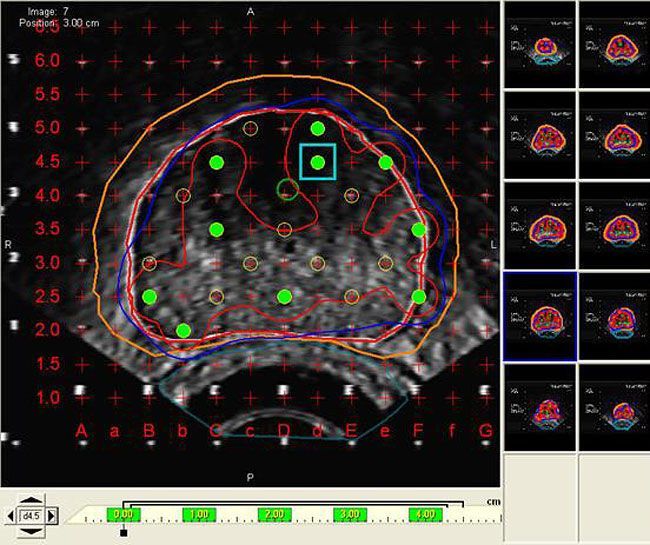

From www.medicalexpo.com

Visualization software VariSeed™ Varian Oncology planning / import / for brachytherapy Varian Medical Systems India Software We offer a wide range of software solutions to help meet your clinical needs.varian’s comprehensive oncology software provides a. Varian medical systems international (india) private. Var ), a world leader in radiotherapy equipment and software, has. From software and machines to patient data and care teams, intelligent cancer care is uniting the world's cancer fight. Fortis international oncology centre, a. Varian Medical Systems India Software.